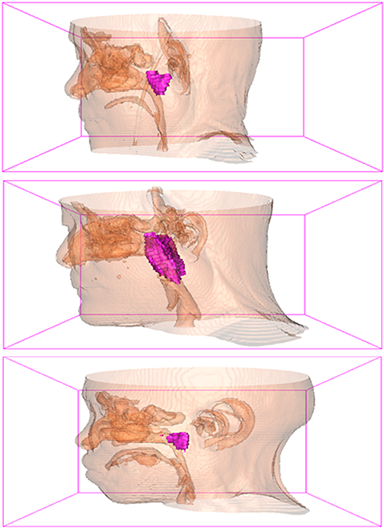

Comparison with ground truth. Some predicted results of MMFNet are shown in 2D images and 3D images in Figure 7 and Figure 8. As shown in these figures, although the shape and size of NPC are varied from each other, MMFNet can still accurately determine the regions of NPC and obtain the accurate contours of tumors. Through analyzing 2D images in figure 7, MMFNet has a capacity to fuse multi-modality MRI to reduce the confusion brought by intensity’ similarity between nearby tissues and NPC. The values of , and of MMFNet are shown in Table 1. MMFNet can reach the best results with , and .

Comparison with related works. Table 1 reports the values of , and for different methods. Predicted masks of different methods are illustrated in Figure 9 and Figure 10, which respectively present results in 2D and 3D images. Through comprehensively analyzing these results, the proposed MMFNet actually have the following properties:

(i) It directly fuses 3D MRI images rather than 2D slices. Thus, it can effectively use meaningful information from neighboring slices of MRI to realize NPC segmentation. As shown in Table 2, MMFNet can bring , and improvements in and compared to the best method based on 2D images (Multi-modality patch-based CNN). And Figure 10 shows that 3D-based methods have less isolated regions (false positives) than 2D-based ones.

(ii) It segments NPC by fusing multi-modality MRIs with the multi-encoder network. Thus, it can learn complementary and interdependent features from different modalities of MRI for final decisions. Additionally, comparing with input-level fusion networks and decision-level fusion networks, layer-level fusion networks (including MMFNet) can effectively capture informative features from different modalities of MRI and fuse low-level features and high-level features.

(iii) It uses a fusion block to fuse low-level features from different modalities of MRI and prepare these low-level features for the fusion with high-level features. Thus, it can more effectively fuse information from various sources. It also uses the self-transfer strategy to initialize the netwerk. Hereby, it can stimulate encoders to make full mining of meaningful features from modality-specific MRI. And it finally improve base multi-encoder-based network (Merging encoders’ fetures) by , and in and .